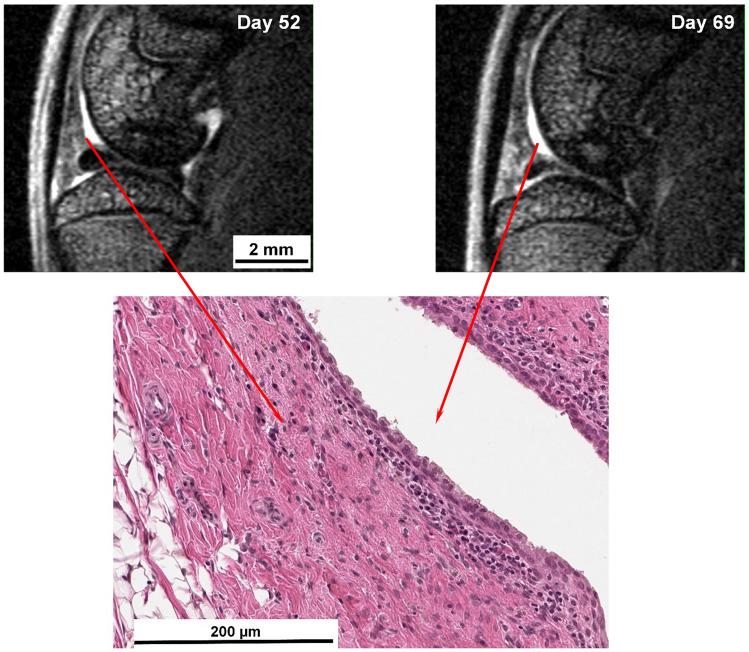

The objective of this work was to assess the consequences of repeated intra-articular injection of monosodium urate (MSU) crystals with inflammasome priming by lipopolysaccharide (LPS) in order to simulate recurrent bouts of gout in rats. Translational imaging was applied to simultaneously detect and quantify injury in different areas of the knee joint. MSU/LPS induced joint swelling, synovial membrane thickening, fibrosis of the infrapatellar fat pad, tidemark breaching, and cartilage invasion by inflammatory cells. A higher sensitivity to mechanical stimulus was detected in paws of limbs receiving MSU/LPS compared to saline-injected limbs. In MSU/LPS-challenged joints, magnetic resonance imaging (MRI) revealed increased synovial fluid volume in the posterior region of the joint, alterations in the infrapatellar fat pad reflecting a progressive decrease of fat volume and fibrosis formation, and a significant increase in the relaxation time T in femoral cartilage, consistent with a reduction of proteoglycan content. MRI also showed cyst formation in the tibia, femur remodeling, and T reductions in extensor muscles consistent with fibrosis development. Repeated intra-articular MSU/LPS injections in the rat knee joint induced pathology in multiple tissues and may be a useful means to investigate the relationship between urate crystal deposition and the development of degenerative joint disease.

本研究旨在评估反复关节内注射单钠尿酸盐(MSU)晶体并预先用脂多糖(LPS)激活炎症小体,以模拟大鼠复发性痛风发作的后果。该研究应用转化影像学技术同时检测和定量评估膝关节不同部位的损伤。MSU/LPS 诱导关节肿胀、滑膜增厚、髌下脂肪垫纤维化、潮线破坏和炎症细胞浸润软骨。与生理盐水注射肢体相比,接受 MSU/LPS 注射的肢体的爪子对机械刺激的敏感性更高。在 MSU/LPS 挑战的关节中,磁共振成像(MRI)显示关节后区滑膜液体积增加,髌下脂肪垫的变化反映了脂肪体积的逐渐减少和纤维化形成,股骨软骨的弛豫时间 T 显著增加,与蛋白聚糖含量减少一致。MRI 还显示胫骨中的囊肿形成、股骨重塑以及伸肌 T 值降低,与纤维化的发展一致。反复关节内 MSU/LPS 注射可诱导大鼠膝关节多种组织的病理变化,可能是研究尿酸盐晶体沉积与退行性关节病发展之间关系的有用手段。